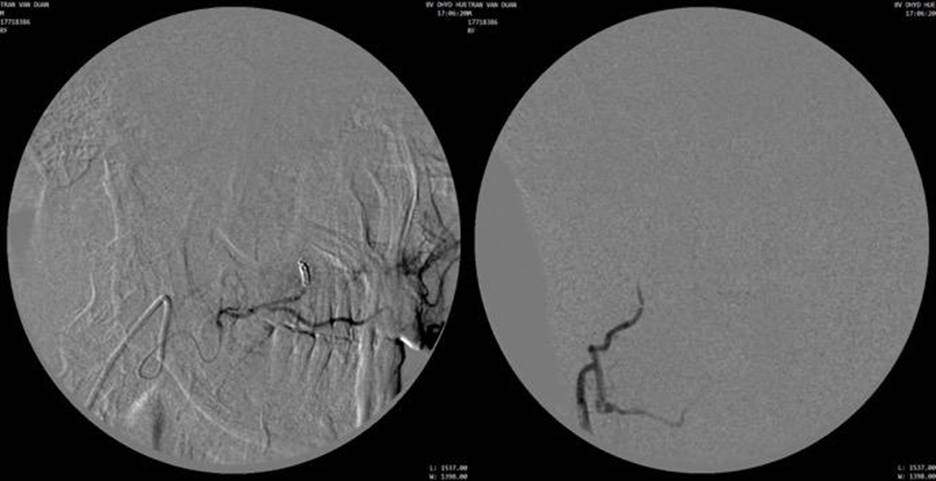

Hình 3: Chụp động mạch mặt phải và chụp chọn lọc nhánh tận động mạch mũi ngoài, khối u ngấm thuốc mạnh, tăng sinh mạch trong u (hypervascularity)

Hình 4: Chụp kiểm tra sau nút mạch bằng hạt PVA và microcoil không còn thấy hình ảnh u ngấm thuốc